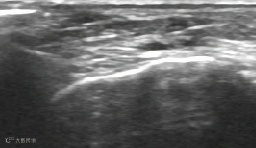

腱鞘囊肿抽液治疗:

治疗前,囊肿大小11X10mm。

治疗后,囊肿消失。